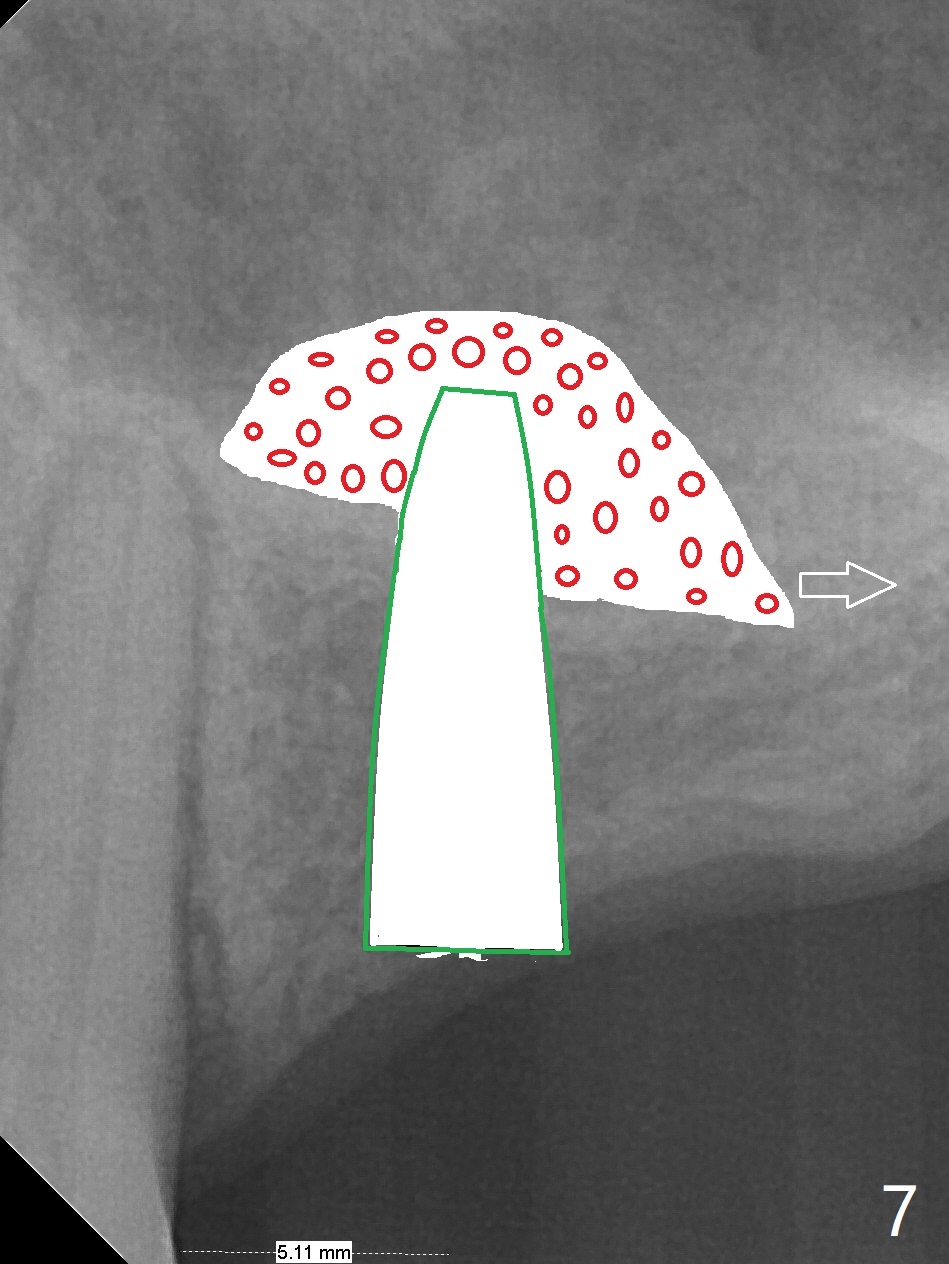

A 57-year-old woman has lost #14,15 and 18 for a while (Fig.1). Because of fear, an implant will be placed at #14 first (Fig.2). After use of Magic Drill for 5 mm (Fig.3), Magic Lifter will be used for lift (Fig.4). Following placement of PRF membrane (Fig.5 blue) and Vanilla Graft (red circles), a dummy implant is placed for additional lift (Fig.6 green). With placement of a larger and probably longer definitive implant, the graft may migrate distal due to gravity in sleep (Fig.7 arrow). In a few months, the bone height at #15 may increase to facilitate implant placement at #15.